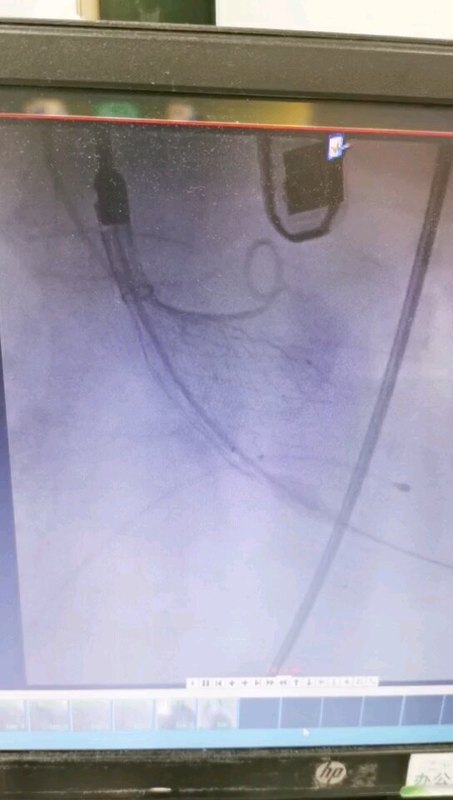

這是一例重度主動(dòng)脈瓣狹窄合并主動(dòng)脈反流的患者,就診于我市多家著名醫(yī)院無(wú)法醫(yī)治。女兒被告知老奶奶已時(shí)日不多。于絕望之中找到了我們團(tuán)隊(duì),順利行微創(chuàng)主動(dòng)脈瓣植入手術(shù)之后,老奶奶已經(jīng)能生活自理,重獲新生。家屬的感激之情,展現(xiàn)于字里行間。其實(shí)我們只是做了我們?cè)撟龅模?

治療前 稍微活動(dòng)就氣促 夜間不能平臥。一般情況差,無(wú)法耐受外科手術(shù)。 治療中 2020年11月3日,微創(chuàng)經(jīng)皮植入人工主動(dòng)脈瓣,術(shù)中檢測(cè)跨瓣壓差明顯改善。 治療后 治療后0天 患者麻醉已蘇醒,預(yù)計(jì)明天可以下地活動(dòng)。氣促癥狀緩解,可以平臥